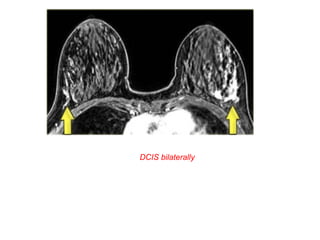

On the left two examples of clumped enhancement in DCIS

Clumped enhancement in DCIS

in two patient

DCIS bilaterally